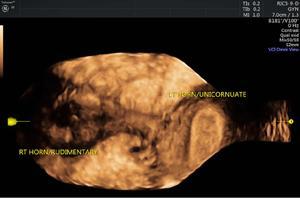

MÜLLERIAN DUCT ANOMALIES Rajani Gorantla Müllerian ducts are a pair of tubular structures that give rise to uterus, cervix, fallopian tubes and upper two-thirds of vagina. Disruption or failure of normal development can result in occurrence of Müllerian duct anomalies (MDAs). These are commonly associated with other congenital anomalies of urinary tract and ovaries due to the close relationship between the development of mesonephric and paramesonephric ducts; few patients also have associated skeletal system anomalies. The prevalence of MDAs in an unselected population was 5.5%; 8% among the infertile women, 12.3% in women with a history of recurrent pregnancy loss and 24.5% in women with miscarriage and infertility. Most of the patients with MDAs are asymptomatic and found incidentally on imaging for any other gynaecological problems, in evaluation of a patient with renal, skeletal or abdominal wall abnormalities. In symptomatic women, complains are related to the type, severity, obstructive anomaly or nonobstructive anomaly. The symptoms can be obstetric or gynaecological related, includes recurrent spontaneous abortions, infertility, preterm labour, intrauterine growth restriction and abnormal foetal lie. Few adolescent girls may present with primary amenorrhoea, hypomenorrhoea, abnormal vaginal bleeding, cyclical pain and mass. Rarely they can present with pelvic inflammatory disease with abnormal vaginal discharge, dyspareunia and urinary tract infections. The female reproductive system develops from a pair of Müllerian or paramesonephric ducts, urogenital sinus and vaginal plate. The ovaries develop separately from the primordial ridge. It is of great importance to understand the normal stages of development, as failure or interruption of any of these stages can lead to a simple to complex spectrum of anomalies. The three stages of Müllerian duct development include: At 6–10 weeks of gestation age, two paired Müllerian ducts and Wolffian ducts formation occurs. When Y chromosome factor (testicular determining factor) is absent, the Wolffian ducts undergo degeneration. The Müllerian ducts further elongate caudally and cross the Wolffian ducts to fuse in the midline. At 10–13 weeks of gestation age, caudal and lateral fusion of the two Müllerian ducts forms primitive uterovaginal canal, which is possessed of solid tissue initially located side by side and further internal canalization leads to the formation of two channels/canals divided by a septum. At this stage, there is reabsorption of the caudal septum and forms single cervical canal and vagina lumen. In around 15–20 weeks of gestation age, complete resorption of the septum takes place in a caudocranial direction from the isthmus to fundus and development of single endometrial cavity results. The fused caudal part of Müllerian ducts gives rise to the uterus, cervix and upper two-thirds of vagina; the unfused cranial part forms the fallopian tubes (Fig. 11.14.1.1). The lower vagina develops from the urogenital sinus, which is separated from the rectum by urorectal septum around 7 weeks of gestation age. The primitive uterovaginal canal embeds into the dorsal wall of urogenital sinus and forms Muller’s tubercle. Around 13 weeks of gestation, two solid masses known as sinovaginal bulbs originate from the upper part of the Muller’s tubercle, further proliferate into the caudal end of the uterovaginal canal to become a solid vaginal plate. Later canalization or degeneration of the central cells of the vaginal plate forms the lower vagina, which is usually completed by 20 weeks’ gestation. The vertical fusion of the upper and lower vagina occurs with resorption of tissue in between and forms single vaginal cavity (Fig. 11.14.1.2). The vaginal lumen is separated from the urogenital sinus by the hymenal membrane. Just before birth, the hymen normally ruptures due to retrogression of the central epithelial cells. However, a thin fold of mucous membrane persists around the vaginal introitus. The ovaries develop separately from migration of primordial germ cells to the genital ridge. Ureteric buds develop separately and concurrently. So renal anomalies are most commonly associated with MDAs with an association of 30%–50%. Various classification systems have been proposed over the past several decades to describe MDAs. Ideally, same classification system needs to be followed by a gynaecologist, surgeon and radiologist for better communication. Buttram and Gibbons classification was suggested in 1979, and it was based upon the level of failure in normal development and segregate the anomalies into groups with similar clinical manifestations, treatment, and prognosis for foetal salvage. According to Buttram and Gibbons, the uterine anomalies were classified into six classes as described in Table 11.14.1.1. The drawback is the lack of classification of vaginal and other anomalies separately. The ASRM (previously the American Fertility Society – AFS) classification system is the most widely accepted classification worldwide over the past years and was introduced in 1988. According to this classification, MDAs are classified into seven classes (class I to class VII) as mentioned in Table 11.14.1.2. However, several limitations have been described by Grimbizis and Campo in 2010 (Fig. 11.14.1.3). The drawbacks of the ASRM classification system are as follows: Hence in 2016, an updated classification of uterine septum, that is ASRM-2016 was proposed and officially approved morphometric criteria are given for distinguishing between septate, normal/arcuate and bicornuate uteri (Table 11.14.1.3). The VCUAM classification was proposed in the year 2005. The main concern is to provide a simple, systematic, clinical classification in addition to providing a precise reflection of the entire malformation. The female genital organs were divided into the following subgroups in accordance with the anatomy: vagina (V), cervix (C), uterus (U) and adnexa (A). Associated malformations were assigned to a subgroup (M) relative to each specific organ. The disadvantage is due to its inherent complexity, and more than 56,700 individual combinations of anomalies are possible. ESHRE and ESGE established a common working group named CONgenital UTerine Anomalies (CONUTA) in order to devise an improved classification system (Table 11.14.1.4). It was published in 2013. Anatomy is the basis for systemic categorization of the MDAs. The subclasses are divided by the different degrees of uterine deformity and their clinical significance (Fig. 11.14.1.4). Cervical and vaginal anomalies are classified into independent supplementary subclasses (Figs. 11.14.1.5–11.14.1.6). For most of the clinicians, it helped as starting point for the development of guidelines for their diagnosis and treatment. The malformations are graded according to severity, U0–U5, C0–C4 and V0–V4, with U5, C4 and V4 being more severe. Class U3 incorporates bicorporeal fusion defects (didelphys and bicornuate) as this was considered as a more functional mode of classification. Arcuate uterus was not included separately, but this is categorized under normal variant into class U1c. Recent studies have demonstrated that the ESHRE/ESGE system provides an effective and comprehensive classification for almost all the currently known MDAs and overcomes the limits of previous classifications. However, there is a relative overdiagnosis of septate uterus with the application of ESHRE–ESGE criteria has been reported and which potentially might lead to unnecessary surgical overtreatment. C0 C1 C2 Normal cervix Septate cervix Double ‘normal’ cervix C3 C4 Unilateral cervical aplasia Cervical aplasia U4 V0 V1 V2 V3 Normal vagina Longitudinal nonobstructing vaginal septum Longitudinal obstructing vaginal septum Transverse vaginal septum and/or imperforate hymen V4 Vaginal aplasia C MDAs’ characterization and classification is of great significance, as the treatment is determined by the type and severity of abnormality. The various imaging modalities available include: HSG was the most recognized imaging modality, earlier to the development of the ultrasonography (USG) and MRI. It is an invasive fluoroscopic-guided procedure for uterine and tubal assessment, and is performed during the midproliferative phase of the cycle, ideally between days 7 and 10 of the cycle when endometrium is thin. Fluoroscopic spot images obtained to evaluate uterine configuration, uterine filling defects and fallopian tube patency. HSG allows evaluation of only the component of the uterine cavity that communicates with the cervix. The anatomic information about myometrium and external fundal contour will not be provided by HSG. The diagnostic criteria used to diagnose MDAs on HSG include: HSG findings of different MDAs are described in Table 11.14.1.5 and Fig. 11.14.1.10. Virtual HSG is a noninvasive technique performed by using a computed tomography (CT) scanner, done 45 s after the contrast material instillation begins. Contraindications are similar to those for HSG and include pregnancy and active pelvic infection. There is no necessity for retraction of the uterus or manipulation of the cervix. The procedure is quick, easy and prophylactic administration of antibiotics is not required. The use of a power injector helps to ensure a steady low pressure of instillation. The procedure is less painful, more comfortable and easily tolerated by patients than conventional HSG. Radiation exposure sometimes requires cervical clamping, which may result in complications such as bleeding and infection. Transabdominal pelvic ultrasound can diagnose uterine anomalies with accuracy rate of 47%. Two-dimensional transvaginal ultrasound (TVUS) has high sensitivity and specificity than transabdominal study and provided some information about external and internal fundal contours. The detection rate is high if the scan is performed in secretory phase due to better visualization of endometrium. Three-dimensional USG shows great accuracy than 2D USG in evaluation of the uterine morphology. The technique of 3D USG varies with different vendors. It displays both the external and internal fundal contours and lower uterine segment by acquisition of single coronal view of uterus (c-view) (Fig. 11.14.1.11). The only disadvantage is that it is transvaginal study and shall not be done in paediatric age group and sexually inactive women. Three-dimensional TVUS has become the first line of screening tool in most of the infertility clinics as it is noninvasive, faster, repeatable, allows storage of volume data and has multiplanar capability for systematic evaluation of the uterine and cervical cavities. The salient features of various Müllerian anomalies on 3D USG are described in Table 11.14.1.6 with images. Three-dimensional ultrasound is combined with sonosalpingography in this technique and provides better delineation of the uterine morphology. It is a less invasive procedure done in proliferative phase with instillation of saline into the uterine cavity and assessment of the uterus will be done. MRI is a universally accepted imaging modality in the documentation of MDAs and accuracy rate of 100% have been reported. MRI provides excellent delineation of both the internal and external uterine anatomies. T2-weighted (T2W) images are the mainstay of pelvic imaging and are performed without fat suppression. T1-weighted (T1W) images are mainly for the haemorrhagic content. The disadvantages of MRI include time-consuming procedure, not cost-effective, large body habitus, pacemakers, recent surgical history and claustrophobia. The current and proposed MRI protocol given by the European Society of Urology (ESUR-MRI protocol) intends a dedicated evaluation of MDAs as mentioned below (Fig. 11.14.1.12): Vaginal anomalies can be accurately diagnosed with the prior administration of the ultrasound gel, to distend vagina (Fig. 11.14.1.13). It will help in better diagnosis of complex vaginal anomalies, like vaginal septations or vaginal duplication. The normal MRI appearance of uterocervical canal and vagina are shown in Fig. 11.14.1.14. Uterine aplasia/hypoplasia/agenesis is class 1 MDA according to ASRM classification and U5 uterine anomaly according to ESHRE classification. It is a formation defect of the paramesonephric ducts with complete or segmental agenesis of uterus and vagina. The incidence rate is around 10%–15% of all MDAs and considered as the most severe form of uterine anomaly. Most of them have complete uterovaginal agenesis with no single completely developed uterine cavity and are associated with Mayer–Rokitansky–Küster–Hauser syndrome (MRKHS). Two types of this syndrome are depicted. The typical form or type A represents the absence or remnants of the uterus, cervix, upper two-thirds of vagina with normal ovaries and fallopian tube (Fig. 11.14.1.15). The atypical form or type B is associated with the abnormalities of the ovaries, fallopian tubes and genitourinary system (Fig. 11.14.1.16). In a few cases (approximately 10%), unilateral or bilateral uterine remnants and with or without endometrial cavity will be seen (Fig. 11.14.1.17). Most of them present with primary amenorrhoea due to complete uterovaginal agenesis and manifest as MRKHS. These patients have normal secondary sexual characteristics due to the preserved normal ovarian function and phenotype. If uterine remnants with functional cavity is present, will present with cyclical pain along with amenorrhoea due to cryptomenorrhoea and haematometra. USG is the first modality for identification of these anomalies, absence of uterus with normal ovaries is diagnostic. But, it is difficult to locate the uterine remnants and cavity due to small acoustic window. MRI is the gold standard and it classifies into uterovaginal agenesis and hypoplasia. If hypoplasia is identified, sagittal and axial sections are taken. These remnants are seen as T2 hypointense tubular structures, located in close relation to ovaries in the adnexa. Once we identify the uterine remnants, it is important to look for the functional endometrial cavity. These will have reduced endometrial and myometrial width. MRI can easily delineate the zonal anatomy due to its high soft tissue contrast resolution. The management of Müllerian agenesis consists of counselling for the patient and her parents. Some patients with MRKHS opt for creation of neovagina for normal sexual life. Various techniques are available. In the presence of a functional Müllerian remnant, regardless of whether it is communicating or not, medical suppression of menses can be initiated and should be followed by laparoscopic removal of the hypoplastic remnant. Unicornuate uterus or hemiuterus is defined as the unilateral uterine development and the contralateral Müllerian duct could be either partially formed or absent. It is a formation defect and the necessity to classify it in a different class than that of uterine agenesis, which is also a formation defect, is due to the existence of a fully developed functional uterine hemicavity. It is considered as class II anomaly according to ASRM classification and class U4 according to ESHRE classification. The frequency rate is around 20% of MDAs. Renal anomalies most often occur in association with unicornuate uterus and usually on the same side of uterine agenesis. Further unicornuate uterus is divided into two subclasses depending on the presence or absence of a functional rudimentary cavity in ESHRE classification: In ASRM classification, unicornuate uterus is divided into four subcategories: Mostly asymptomatic and presence of the noncommunicating uterine remnants will be identified at the time of infertility work up or caesarean section. If a functional cavity is present, the presentation is dysmenorrhoea or haematometra in an adolescent. The common obstetrics-related complications include abnormal foetal lie, intrauterine growth retardation, preterm delivery, placental abnormalities and uterine rupture. Gynaecological complications are ectopic pregnancy and endometriosis due to retrograde menstruation. On imaging, unicornuate uterus is seen as tubular and fusiform or banana-shaped structure at paramedian location, the endometrium is narrow and tapers to the apex with normal myometrial anatomy and reduced uterine volume. The rudimentary cavity or remnants are better depicted on 3D USG (Fig. 11.14.1.18) and MRI. However, MRI is superior to USG due to its high soft tissue resolution. The rudimentary cavity can communicate with main cavity or connected by fibrous band. The nonfunctioning cavity will be seen as T2 hypointense structure with loss of zonal anatomy (Figs 11.14.1.19 and 11.14.1.20), whereas the functioning cavity will show the deformed zonal anatomy (Fig. 11.14.1.21), and its complications like haematometra as T1/T2 hyperintense endometrial collection. Unicornuate uterus without rudimentary cavity does not require any procedure. But in the presence of communicating or noncommunicating rudimentary horn, surgical resection must be considered to prevent complications. Uterine didelphys is a class III MDA based on the ASRM classification and class U3b bicorporeal uterus according to ESHRE classification with an incidence rate of 5% among the uterine anomalies. It is a lateral fusion defect; results from complete failure of the Müllerian duct fusion. Two noncommunicating endometrial cavities with preserved zonal anatomy are seen with separate cervix. According to ESHRE classification, it is defined as external fundal indentation completely dividing the uterine corpus up to the level of external cervical os. It is most commonly associated with longitudinal vaginal septum in around 75% of cases. Some patients may show transverse vaginal septum and these will be obstructive or nonobstructive type. Renal anomalies are also commonly associated with uterine didelphys. Uterine didelphys is usually asymptomatic and diagnosed incidentally on pelvic examination or caesarean section. The uterine didelphys with obstructed vagina (Fig. 11.14.1.22) will present at adolescence as dysmenorrhoea, haematometrocolpos and haematosalpinx. Sometimes retrograde menstrual flow can cause endometriosis and pelvic adhesions. Obstetric-related complications include abortion/foetal growth restriction and poor pregnancy outcome. The uterine didelphys with obstructed hemivagina due to transverse vaginal septum and associated ipsilateral renal agenesis are the manifestations of the syndrome called obstructed hemivagina and ipsilateral renal agenesis anomaly/Herlyn–Werner–Wunderlich (HWW) syndrome (Fig. 11.14.1.23).